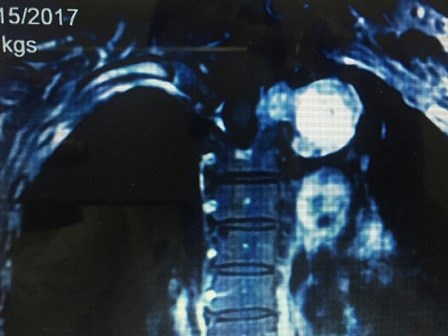

Tuỷ sống mọc u to như quả cam

Điều trị đau lưng, vai một thời gian dài nhưng không có hiệu quả, khi chụp cộng hưởng từ phát hiện khối u trong tuỷ sống to bằng quả cam.